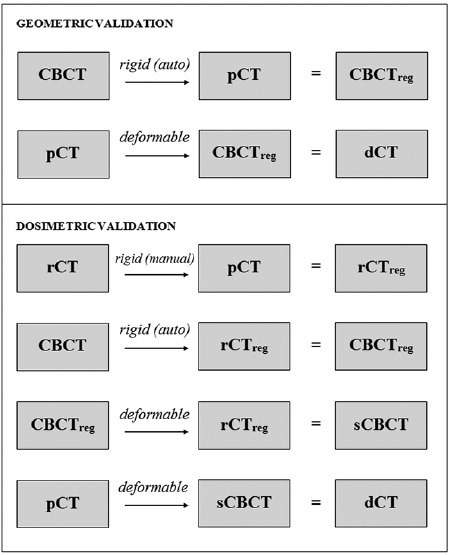

Dosimetric validation—voxelwise dose differences

The dosimetric validation tests the reliability of dose calculations carried out on the registered image data. To validate the registrations dosimetrically, dose distributions calculated on the dCT images were compared with gold standard dose distributions calculated on the rCTs. To obtain the gold standard distribution, rCT images were rigidly registered to pCT images manually by a single operator. Registrations matched the bony anatomy in the region of the tumour in line with clinical protocols, the aim being to create a gold standard dose distribution that reflected anatomical changes only, not setup errors.

Each CBCT-rCT pair was acquired using different modalities at different times, such that non-negligible positional and anatomical differences existed between these images. This meant that even if the pCTs were perfectly deformed to the CBCTs, the resulting dCT images would still differ from the gold standard rCT images. To mitigate the corrupting effects of these differences on the dosimetric validation, simulated CBCT (sCBCT) images were first produced by deformably registering the CBCTs to the rCTs (Veiga et al 2014). These sCBCTs were then used in place of the original CBCT images as the targets for the deformation. All sCBCTs were visually inspected to ensure they represented the rCT anatomy more closely than the original CBCT images. The dCT images were then created by registering the pCTs to the sCBCTs. A summary of the registrations that were carried out to produce the deformed images is shown at figure 3.

Figure 3. Pipeline of the registrations carried out to produce deformed pCT images (dCTs) for validation.

Download figure:

Standard image High-resolution imageDose calculations were carried out on the Eclipse (Varian Medical Systems, Palo Alto, CA) treatment planning system (TPS) using the analytical anisotropic algorithm. Details of the original pCT treatment plan, including beam arrangement, fluence maps and monitor units were copied onto the dCT and rCT. All dose calculations were performed at a resolution of 1 mm.